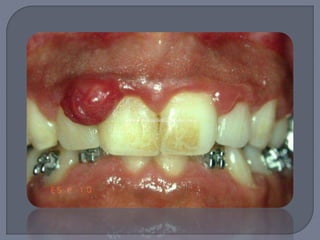

Lesión elevada localizada de tejido de

granulación

Aparece en diversas áreas de la mucosa y piel,

siendo la encía la localización más común

junto con labios y dorso de la lengua

Masa exofítica a veces lobulada y ulcerada

Por lo general pedículada

Color rojo o rojo púrpura

Tendencia a sangrado

Diámetro de milímetros a centímetros

Es necesaria la extirpación quirúrgica de toda

la lesión

Si involucra dientes debe hacerse raspado y

alisado

Si la lesión recidiva entonces es probable que

haya que extraer el diente involucrado

Cuando se da durante el embarazo se le llama

“ tumor del embarazo” o “ épulis del

embarazo” o “granuloma gravídico”

Suele iniciar en el primer trimestre y va

creciendo

Sobre todo si es pequeño desaparece después

del parto

En algunas ocaciones se extirpa por razon funcionales

o estéticas o por sangrado frecuente